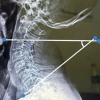

Laboratory findings included increased white blood cell count and erythrocyte sedimentation rate of 78 mm/1st h and C-reactive protein of 18.8 mg/dL. Blood culture was positive for methicillin-susceptible S. aureus. CT scan revealed a fluid collection in the left SCJ and bony erosions and a periosteal reaction of the clavicular head and sternal body (Fig. 2). Retrosternal spread of infection was excluded from the study.